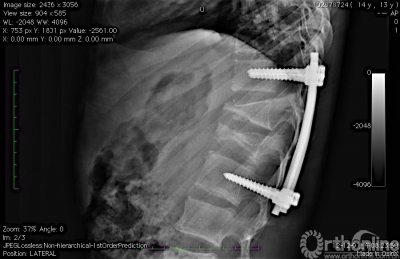

图 2 术后腰椎侧位片,L2椎体病变刮除彻底,植骨充分,内植物位置良好。

图3 术后1年腰椎侧位片,L2椎体高度部分恢复。